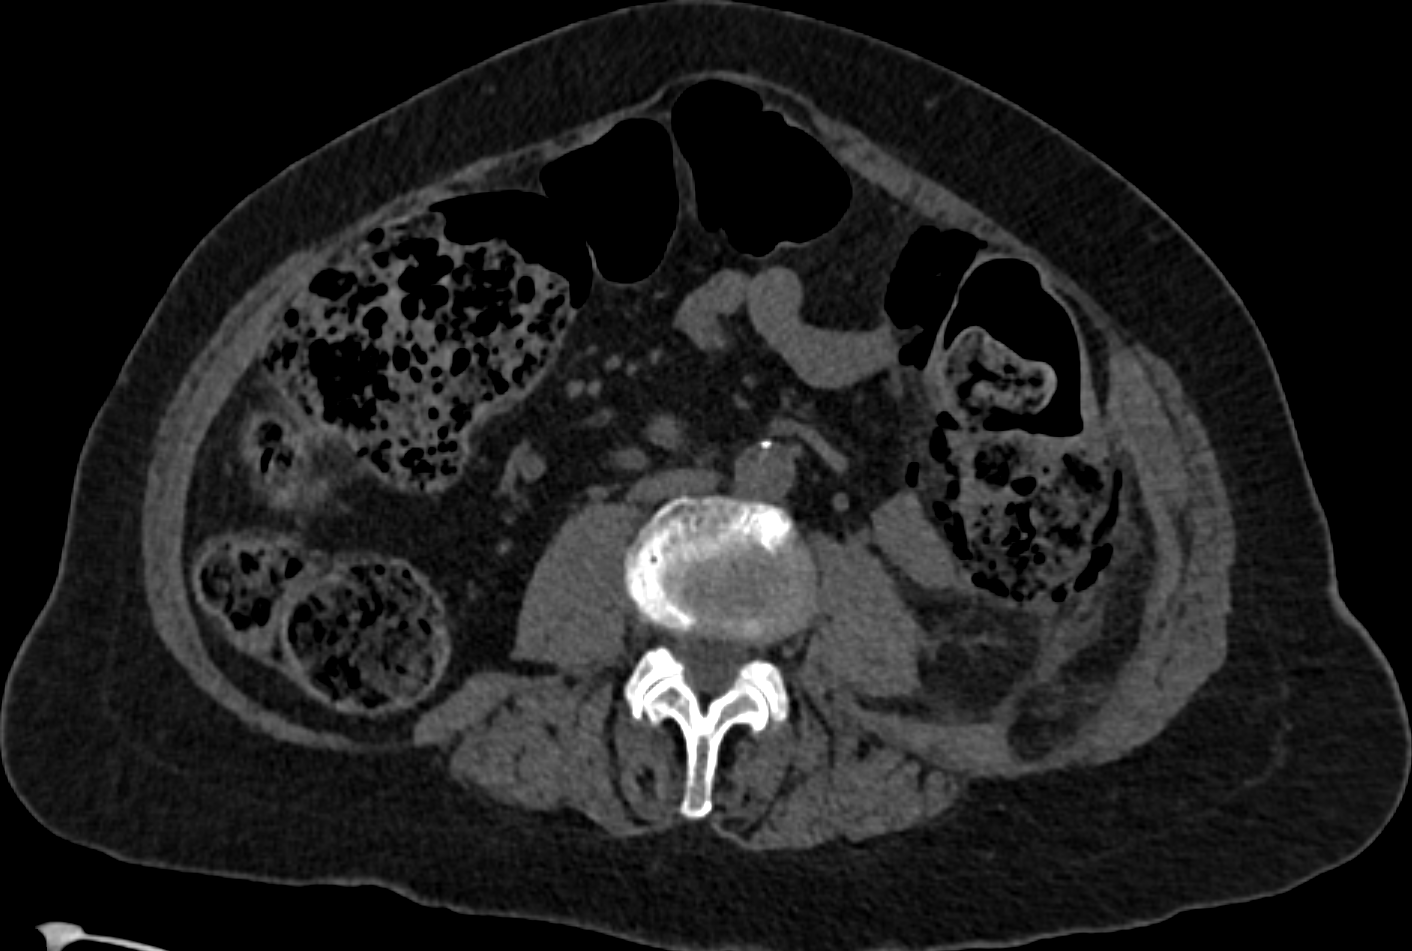

3. Stercoral perforation